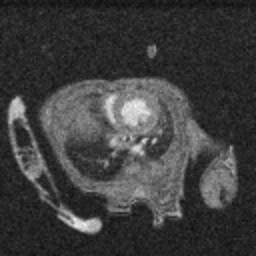

Cardiac Cine loop images: Long axis view of a single slice of the heart was acquired with Cine loop images. Long axis images can be used for strain analysis in third party softwares.

Cardiac Cine loop images: Long axis view of a single slice of the heart was acquired with Cine loop images. Long-axis images can be used for strain analysis in third-party software. Image Credit: Scintica Instrumentation Inc

Short axis view of a single slice of the heart was acquired with Cine loop images. Short axis images can be used for analysis of functional measurements in third party softwares

Short axis view of a single slice of the heart was acquired with Cine loop images. Short axis images can be used to analyze functional measurements in third-party software. Image Credit: Scintica Instrumentation Inc